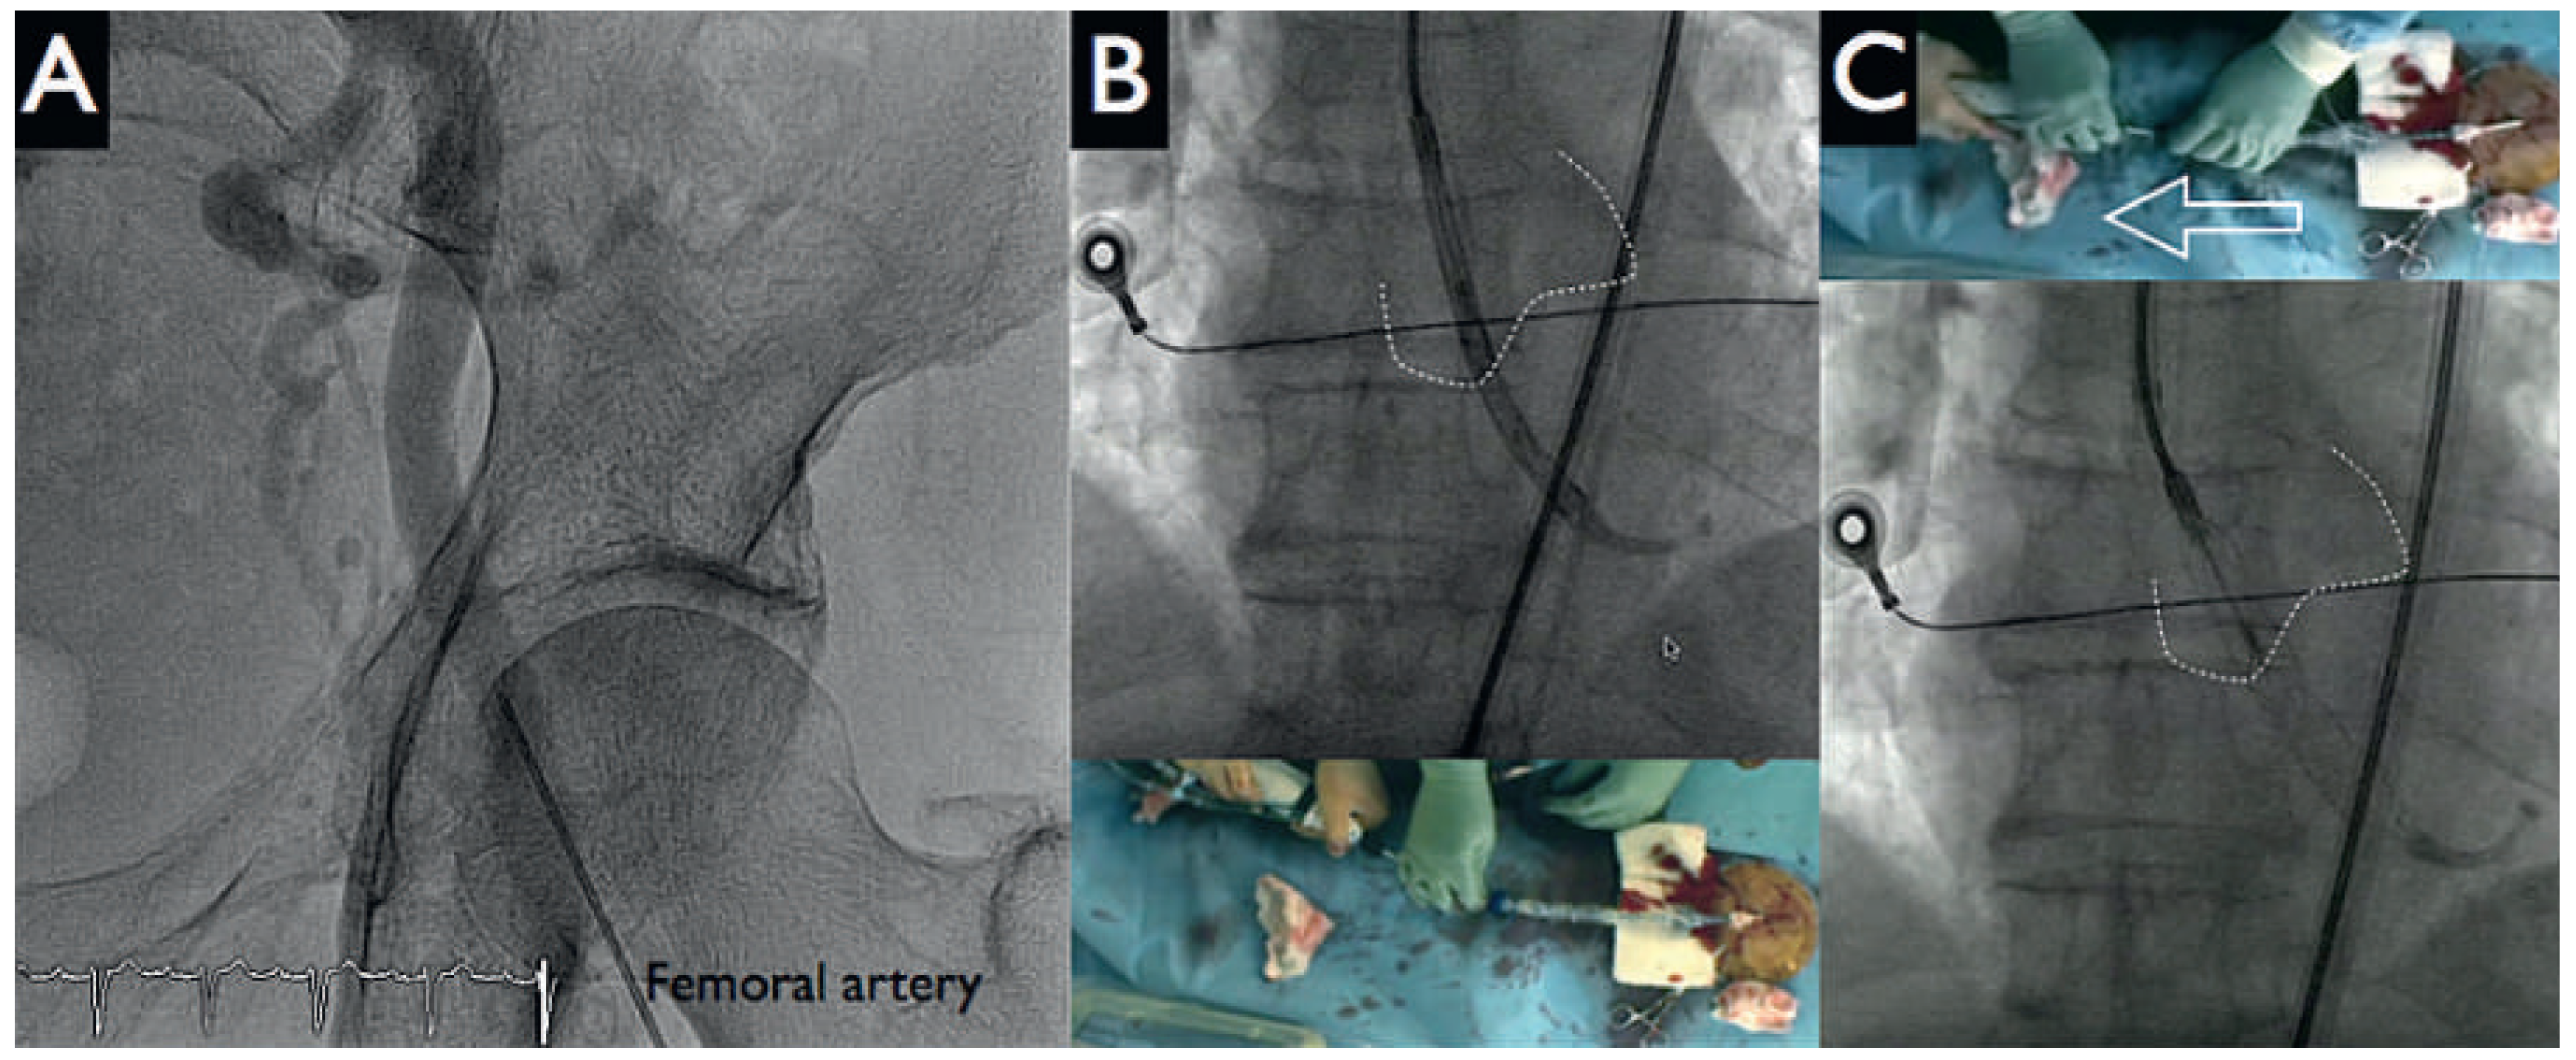

Figure 5. HeartMate PHP re-sheath. Panels A, B: the conduit was easily re-sheathed into the catheter by pulling down the pump into the sheath. Panel C: tightening of the two Proglides completed haemostasis.

Following this, the pigtail catheter was exchanged for a 6 Fr Q4 guiding catheter with PCI of the distal left anterior descending artery (LAD) (SYNERGY II 2.25–20 mm, Boston Scientific, Figure 4 panel B left) and proximal LAD to distal left main artery (SYNERGY II 4.00–38 mm, Boston Scientific, Figure 4 panel B right) with T-stenting into the left circumflex artery (SYNERGY II 2.75–12 mm, Boston Scientific, Figure 4 panels B, E). Postdilatation with kissing balloon inflation (4.00–15 mm in LAD, 2.75–12 mm in the left circumflex artery) demonstrated a good final angiographic result (Figure 4 panels C, F). During the intervention no significant haemodynamic changes were noted, and the patient tolerated the balloon inflations well. The HeartMate-PHP was then gently removed into the descending aorta. The pump was stopped and the conduit could be easily resheathed into the catheter (Figure 5 panels A, B). Haemostasis was achieved with tightening of the two Perclose (Figure 5 panel C) and the patient was given a loading dose of 60 mg prasugrel.